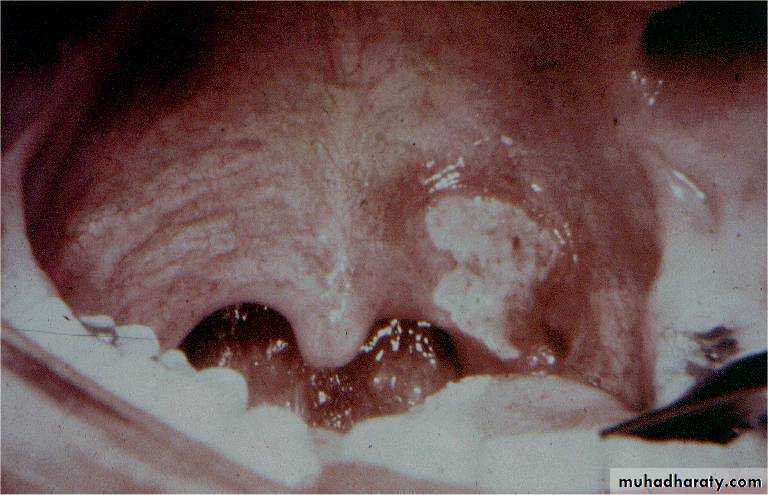

Adenoids

The adenoids lie between the roof and posterior wall of the nasopharynx.

Adenoids differ from tonsillar tissue in that it's bounded by no capsule, contains no crypts and covered by ciliated epithelium.Hypertrophy of the nasopharyngeal tonsil, sufficient to produce symptoms, most commonly between 3-7 years of age.

Symptoms

A-Nasal- Nasal obstruction, mouth breathing, snoring , in severe cases: OSA.

- Persistent nasal discharge & postnasal drip. The child may be described as " always having a cold".

- Nasal speech (rhinolalia clausa).

B- Aural

Recurrent attacks of otitis media and otitis media with effusion.C-General

Failure to thrive, mental dullness.Pharyngitis and recurrent URTI

Examination

I. Adenoid facies.1. Open mouth.

2. Prominent upper

incisor teeth.

3. Short upper lip.

4. Narrow nostrils.

5. Hypoplastic maxilla.

6. High arched palate.

7. Dull expression due to hypoxia and deafness.

2. Mucoid and mucopus discharge from the nose with postnasal catarrh.

3. Posterior rhinoscopy and fibroptic endoscopy: lobulated mass, which occasionally extends laterally.Investigations